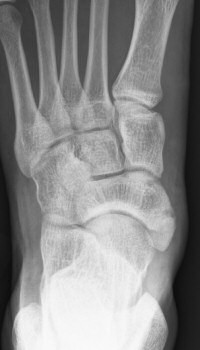

Första bilden med normal navikulare, andra bilden med accessorisk navikulare typ 2, tredje bilden typ 3.